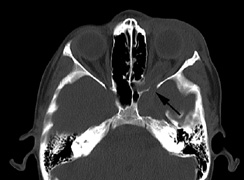

CNS hemangiomas are the most common tumor of VHL, affecting 60% to 80%, with a predilection for the cerebellum and spinal chord. An enlarging cystic component is a frequent finding in symptomatic tumors. Patients typically present in their early 30s; headaches or neck pain in affected individuals should not be ignored.172,173 On microscopy, CNS hemangiomas resemble retinal capillary hemangiomas. Their malignant potential is low.174 The treatment is surgical (Fig. 17, A and B).13

Fig. 17. Images from a 13-year-old boy with Von Hippel-Lindau syndrome. (a) Coronal postcontrast T1-weighted imaging reveals a cystic lesion with an enhancing nodule at the pial surface typical of a hemangioblastoma. (b) A second solid enhancing hemangioblastoma is seen at the craniocervial junction on a sagittal postcontrast T1-weighted image. (c) Associated cystic lesions (arrows) are seen within the pancreas.

Pancreatic lesions may be nonsecretory (most commonly cysts or cystadenomas) or secretory (islet cell tumor).179 In one study of 52 patients, 56% (29 patients) were found to have pancreatic lesions. The majority (19 of 29) had cystic changes only (Fig. 17C). Pancreatic lesions were the only abdominal manifestation of disease in 6 of 52 patients.180 In a separate study, pancreatic cysts did not show significant progression on follow-up examinations over an average period of 5 years.181 Like pancreatic cysts, islet cell tumors appear to be frequently asymptomatic.182